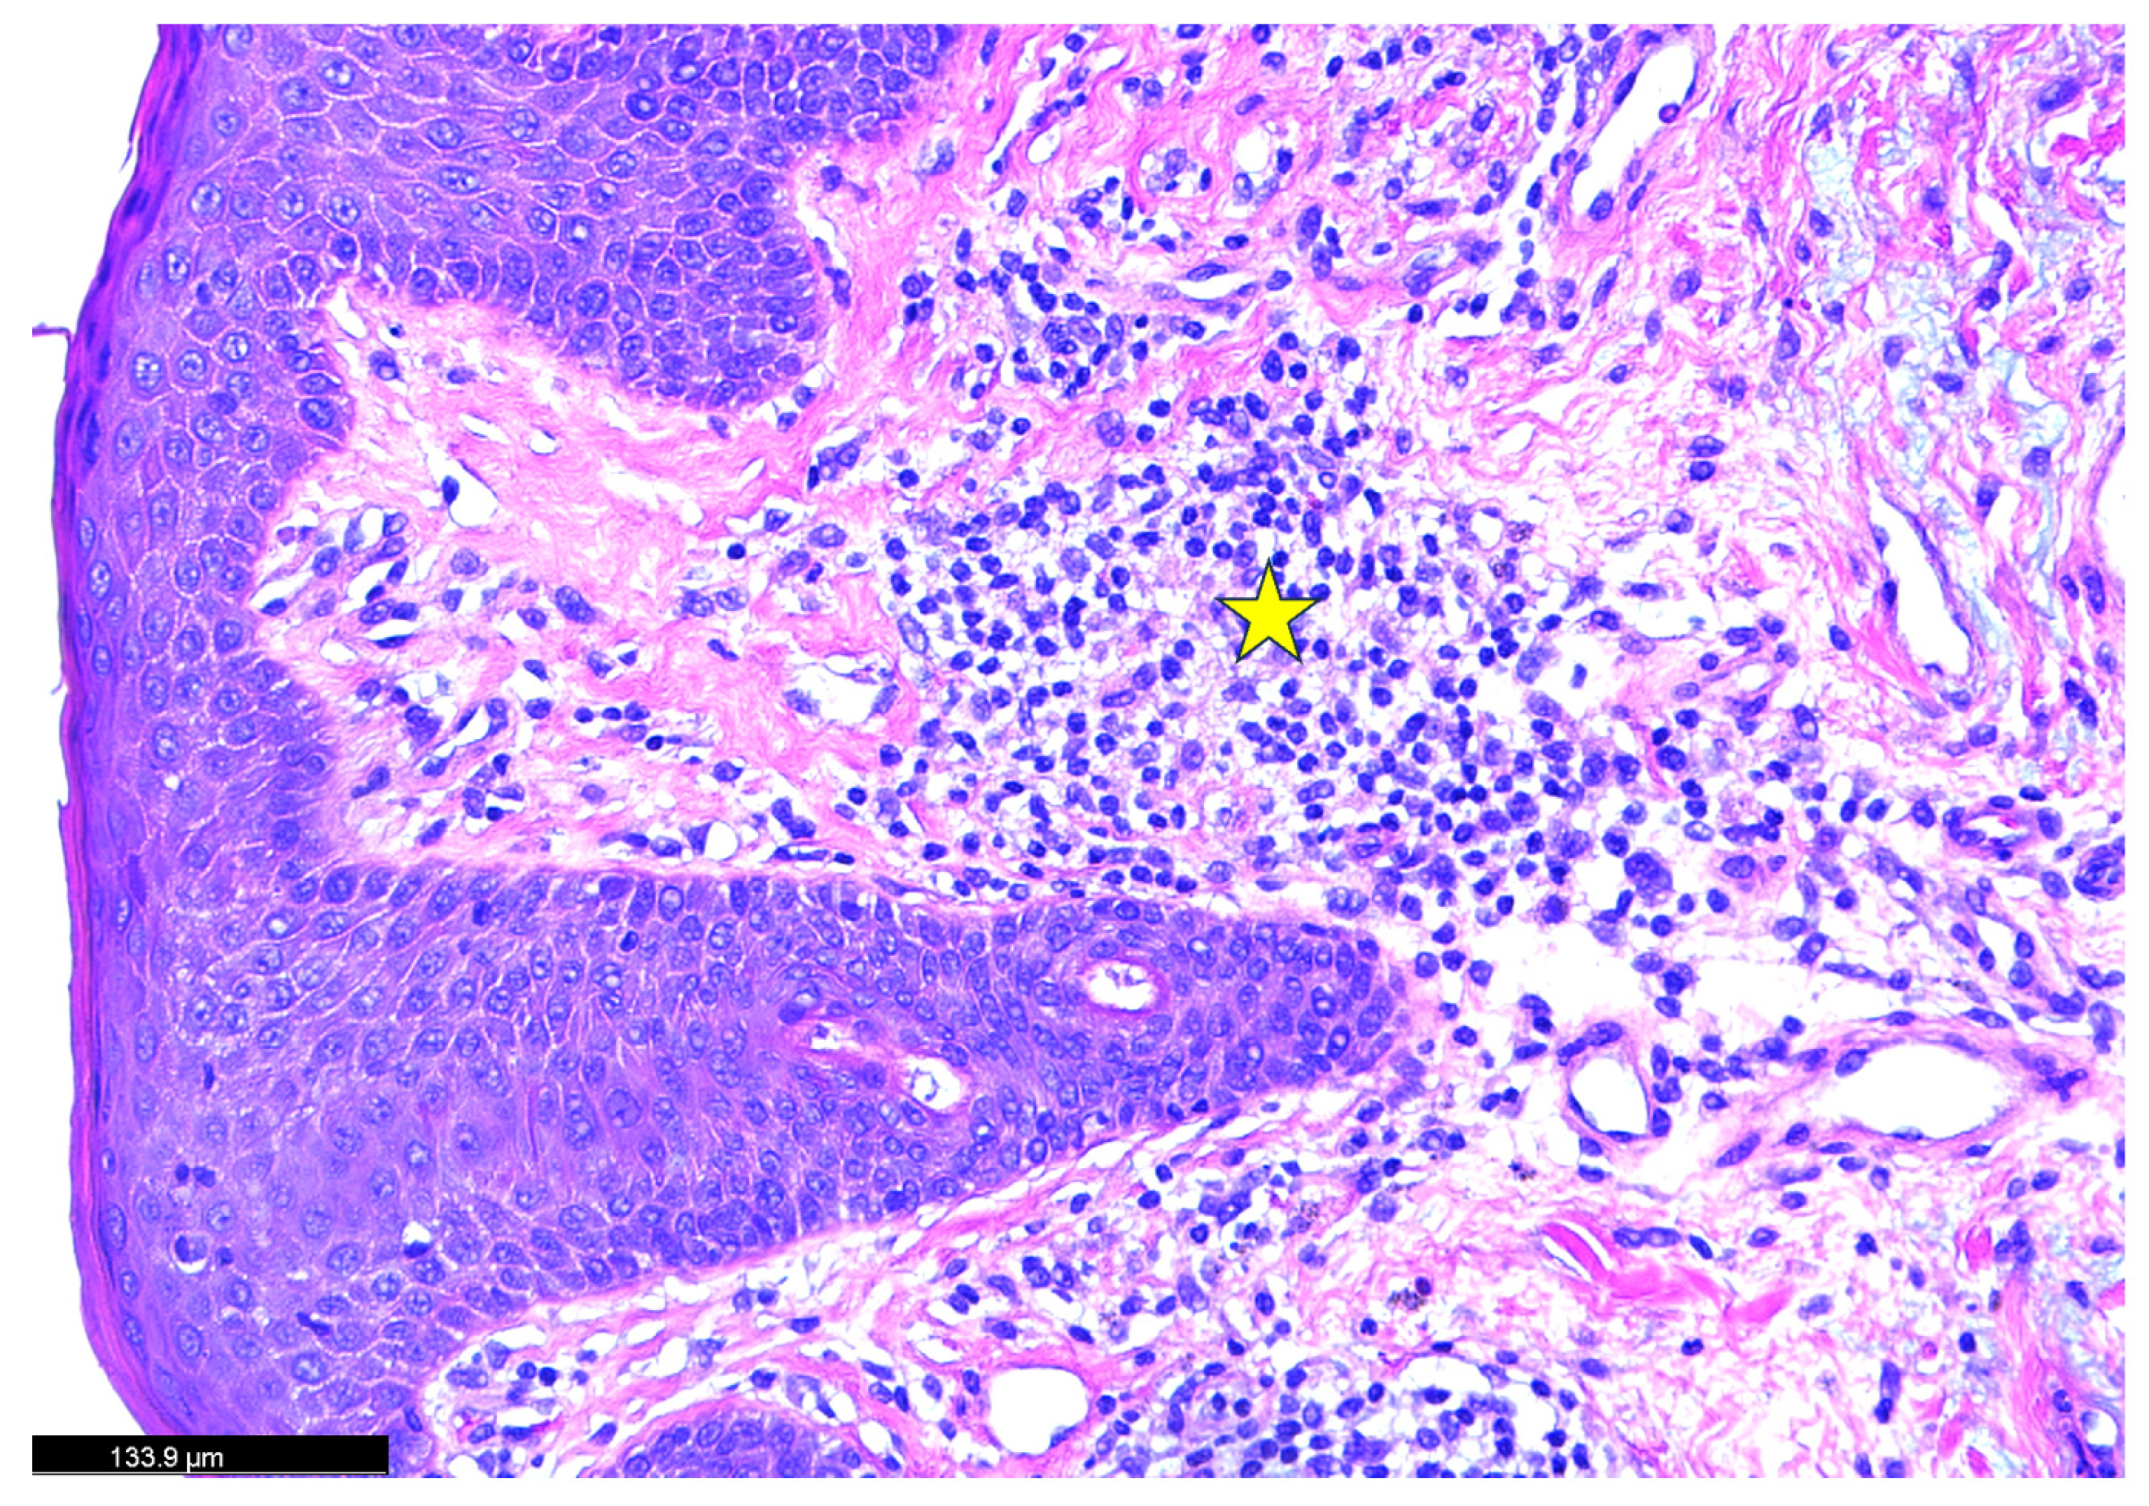

2. Case Study